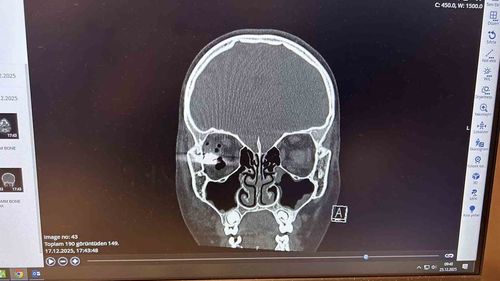

Beynine mermi isabet eden 10 yaşındaki Ahrorbek Hojimurodov, Memorial Ataşehir'de nöronavigasyon teknolojisiyle yapılan operasyonla sağlığına kavuştu; görme kurtarılma umudu sürüyor.

Nöronavigasyonla Operasyon: Beynine Mermi Saplanan Çocuk Sağlığına KavuştuMemorial Ataşehir'de kapalı yöntemle gerçekleştirilen ameliyatla 10 yaşındaki Ahrorbek Hojimurodov’un hayatı kurtarıldıÖzbekistan uyruklu 10 yaşındaki Ahrorbek Hojimurodov, Aralık 2025 tarihinde evde kuzeni ile oynadığı silahın ateş alması sonucu beynine mermi isabet etti. Mermi,…